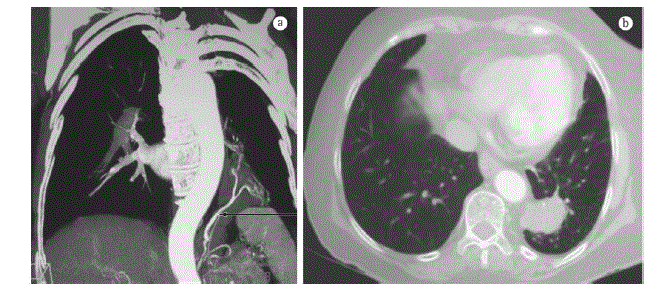

Paciente de 10 anos de idade vem evoluindo com episódios de infecções de repetição no último ano, necessitando de internamento hospitalar no último episódio. Recebeu alta hospitalar e iniciou acompanhamento com pneumopediatra que solicitou tomografia de tórax para investigação.

Diante da imagem da tomografia, qual a principal hipótese diagnóstica e o tratamento a ser instituído?